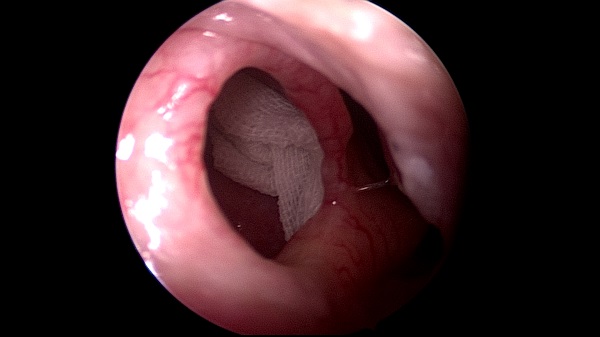

耳鼻咽喉頭頸外科(ke)近日(ri)成(cheng)功爲(wei)一(yi)名(míng)“慢性鼻窦炎伴鼻息肉鼻中(zhong)隔穿孔鼻中(zhong)隔偏曲 ”的(de)中(zhong)年(nian)男性患者,行全麻“鼻內(nei)窺鏡下低溫等(deng)離子(zi)刀(dāo)全組鼻窦開放+窦內(nei)病變清(qing)除術(shù)+雙側鼻息肉切除術(shù)+鼻中(zhong)隔穿孔修補術(shù)+鼻中(zhong)隔偏曲矯正術(shù)+雙側下鼻甲骨折外移術(shù)”。

術(shù)中(zhong)遊離鼻中(zhong)隔穿孔前(qian)、後(hou)、上、下緣黏軟骨膜,取方(fang)形軟骨部(bu)分(fēn)篩骨垂直闆部(bu)分(fēn)犁骨組織修補穿孔松解穿孔周圍黏膜瓣并保留血供,穿孔被完全覆蓋(gai),去除鼻中(zhong)隔左側偏曲的(de)篩骨垂直闆,開放雙側上颌窦、額窦、篩窦、左側蝶窦清(qing)除窦內(nei)病變,去除雙側中(zhong)鼻道息肉。術(shù)程(cheng)順利,無副損傷。術(shù)後(hou)患者恢複良好,病人(ren)目(mu)前(qian)已出院。